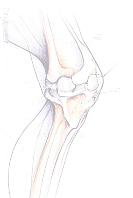

Найточніша діагностика в Україні

Обладнання рівня преміальних клінік і сертифіковані лікарі